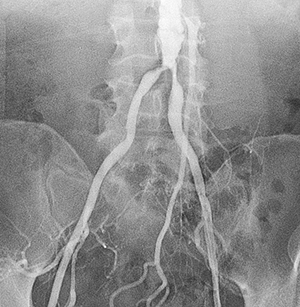

Angiogram of abdominal aorta and iliac arteries.

Peripheral angiography is a test that uses X-ray and dye (contrast material) to map the blood vessels (arteries) in your lower body, legs, and arms. This map can show where blood flow may be blocked.